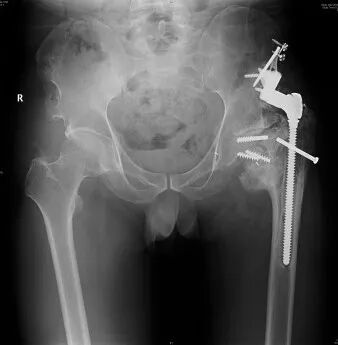

家人帶著魯阿姨找到了省級知名骨科專家、邦爾骨科集團首席專家、嘉興邦爾骨科醫(yī)院院長趙凱教授,診斷為“雙側(cè)先天性髖關(guān)節(jié)脫位+雙側(cè)股骨頭無菌性壞死”,并進行了“右側(cè)先天性髖關(guān)節(jié)脫位髖臼重建術(shù)+全髖關(guān)節(jié)置換術(shù)+截骨矯形術(shù)”,術(shù)后患者恢復(fù)良好,能夠正常行走。

術(shù)前顯示:左側(cè)髖關(guān)節(jié)被腫瘤侵蝕嚴(yán)重

術(shù)后假體位置良好